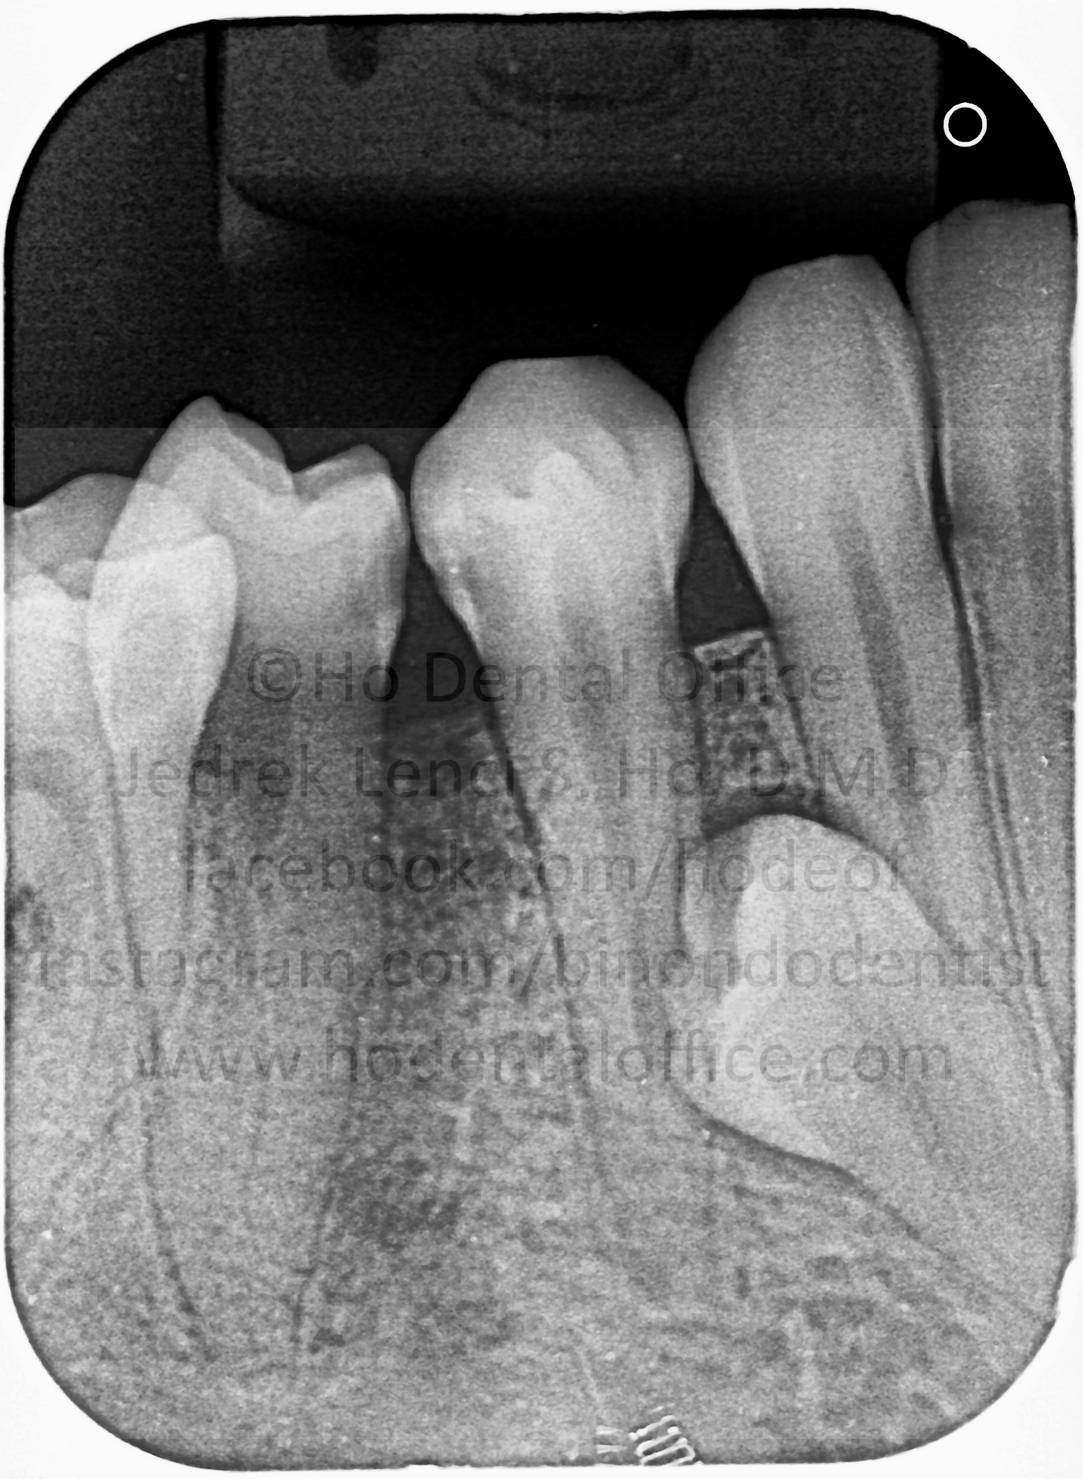

upper canine tooth

- Since the canines are very important foundational tooth crucial to the shape and anatomy of the face, most dentists / orthodontists would attempt to surgically expose and orthodontically align them into their proper position.

orthodontically assisted tooth eruption for impacted canines - gold chain bonded on impacted canines with elastic traction tied to nearby tooth/wire